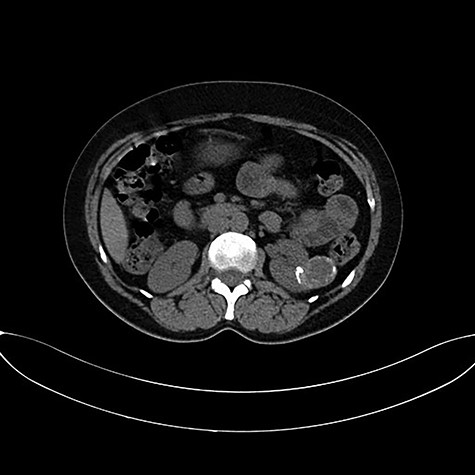

Abdominal ultrasound and computed tomography showed a 3-cm cystic lesion occupying the mid zone of the left kidney with a thickened irregular wall, calcifications, partially contrast enhancement and without secondary locations. The right kidney and other organs were normal. This renal lesion was diagnosed as cystic renal cell carcinoma (Fig. 1).